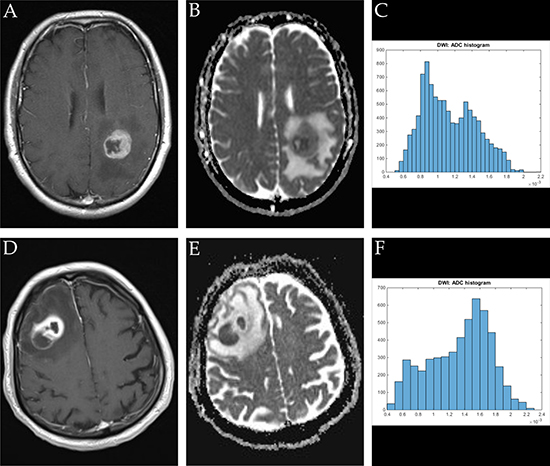

ADC volume histogram analysis gave the following values for the overall collective (each median (range) and mean value ± standard deviation, all in x 10−5 mm2 x s−1): ADCmin = 24.700 (101.20), 27.39 ± 25.94, ADCmean = 120.66 (148.53), 124.36 ± 31.18, ADCmax = 283.70 (290.50), 275.06 ± 55.81, ADCp10 = 77.60 (341.40), 80.89 ± 37.18, ADCp25 = 92.65 (110.60), 93.68 ± 25.40, ADCp75 = 147.50 (200.30), 149.95 ± 42.63, ADCp90 = 172.63 (218.18), 199.36 ± 203.90, ADCmedian = 117.40 (875.20), 127.13 ± 86.37, ADCmodus = 106.30 (282.20), 111.41 ± 51.29. Evaluation of histogram-based characteristics of the investigated volumes for the overall collective gave the following values (each median (range) and mean value ± standard deviation): skewness = 0.581 (5.86), 0.69 ± 0.79, entropy = 4.59 (2.59), 4.49 ± 0.59 and kurtosis = 3.10 (22.19), 4.10 ± 3.27. Figures 1, 2 and 3 provide examples of ADC maps (B, E) coregistered to corresponding T1 weighted post contrast images (A, D) and the respective whole lesion histograms (C, F) of morphologically similar appearing GBM and BA in frequently encountered locations. Table 1 summarizes the findings in the overall collective.

Figure 3: Imaging findings and corresponding ADC-histograms of morphologically resembling manifestations of GBM (left-sided parietal) and brain abscess (right-sided dorso-lateral prefrontal cortex). The upper row shows a representative axial T1 weighted post contrast image (A), the corresponding ADC map (B) and the whole lesion ADC-histogram (C) of GBM in a 53 years old male patient. The evaluated parameters were as follows (ADC parameters all in 10−5 mm2 × s-1): ADCmean: 113.21, ADCmin: 52.30, ADCmax: 217.40, ADCp10: 76.70, ADCp25: 87.70, ADCp75: 136.80, ADCp90: 157.00, ADCmedian: 108.30, ADCmodus: 89.00, Kurtosis: 2.25, Skewness: 0.38, Entropy 4.55. The inferior row shows a representative axial T1 weighted post contrast image (D) of brain abscess in a 80 years old male patient, the corresponding axial ADC map (E) and the respective whole lesion ADC-histogram (F). Evaluated parameters were as follows (ADC parameters all in 10-5 mm2 × s-1): ADCmean: 133.02, ADCmin: 46.60, ADCmax: 224.80, ADCp10: 71.80, ADCp25: 101.95, ADCp75: 163.00, ADCp90: 179.39, ADCmedian: 141.00, ADCmodus: 160.90, Kurtosis: 2.20, Skewness: -0.33, Entropy: 3.92.